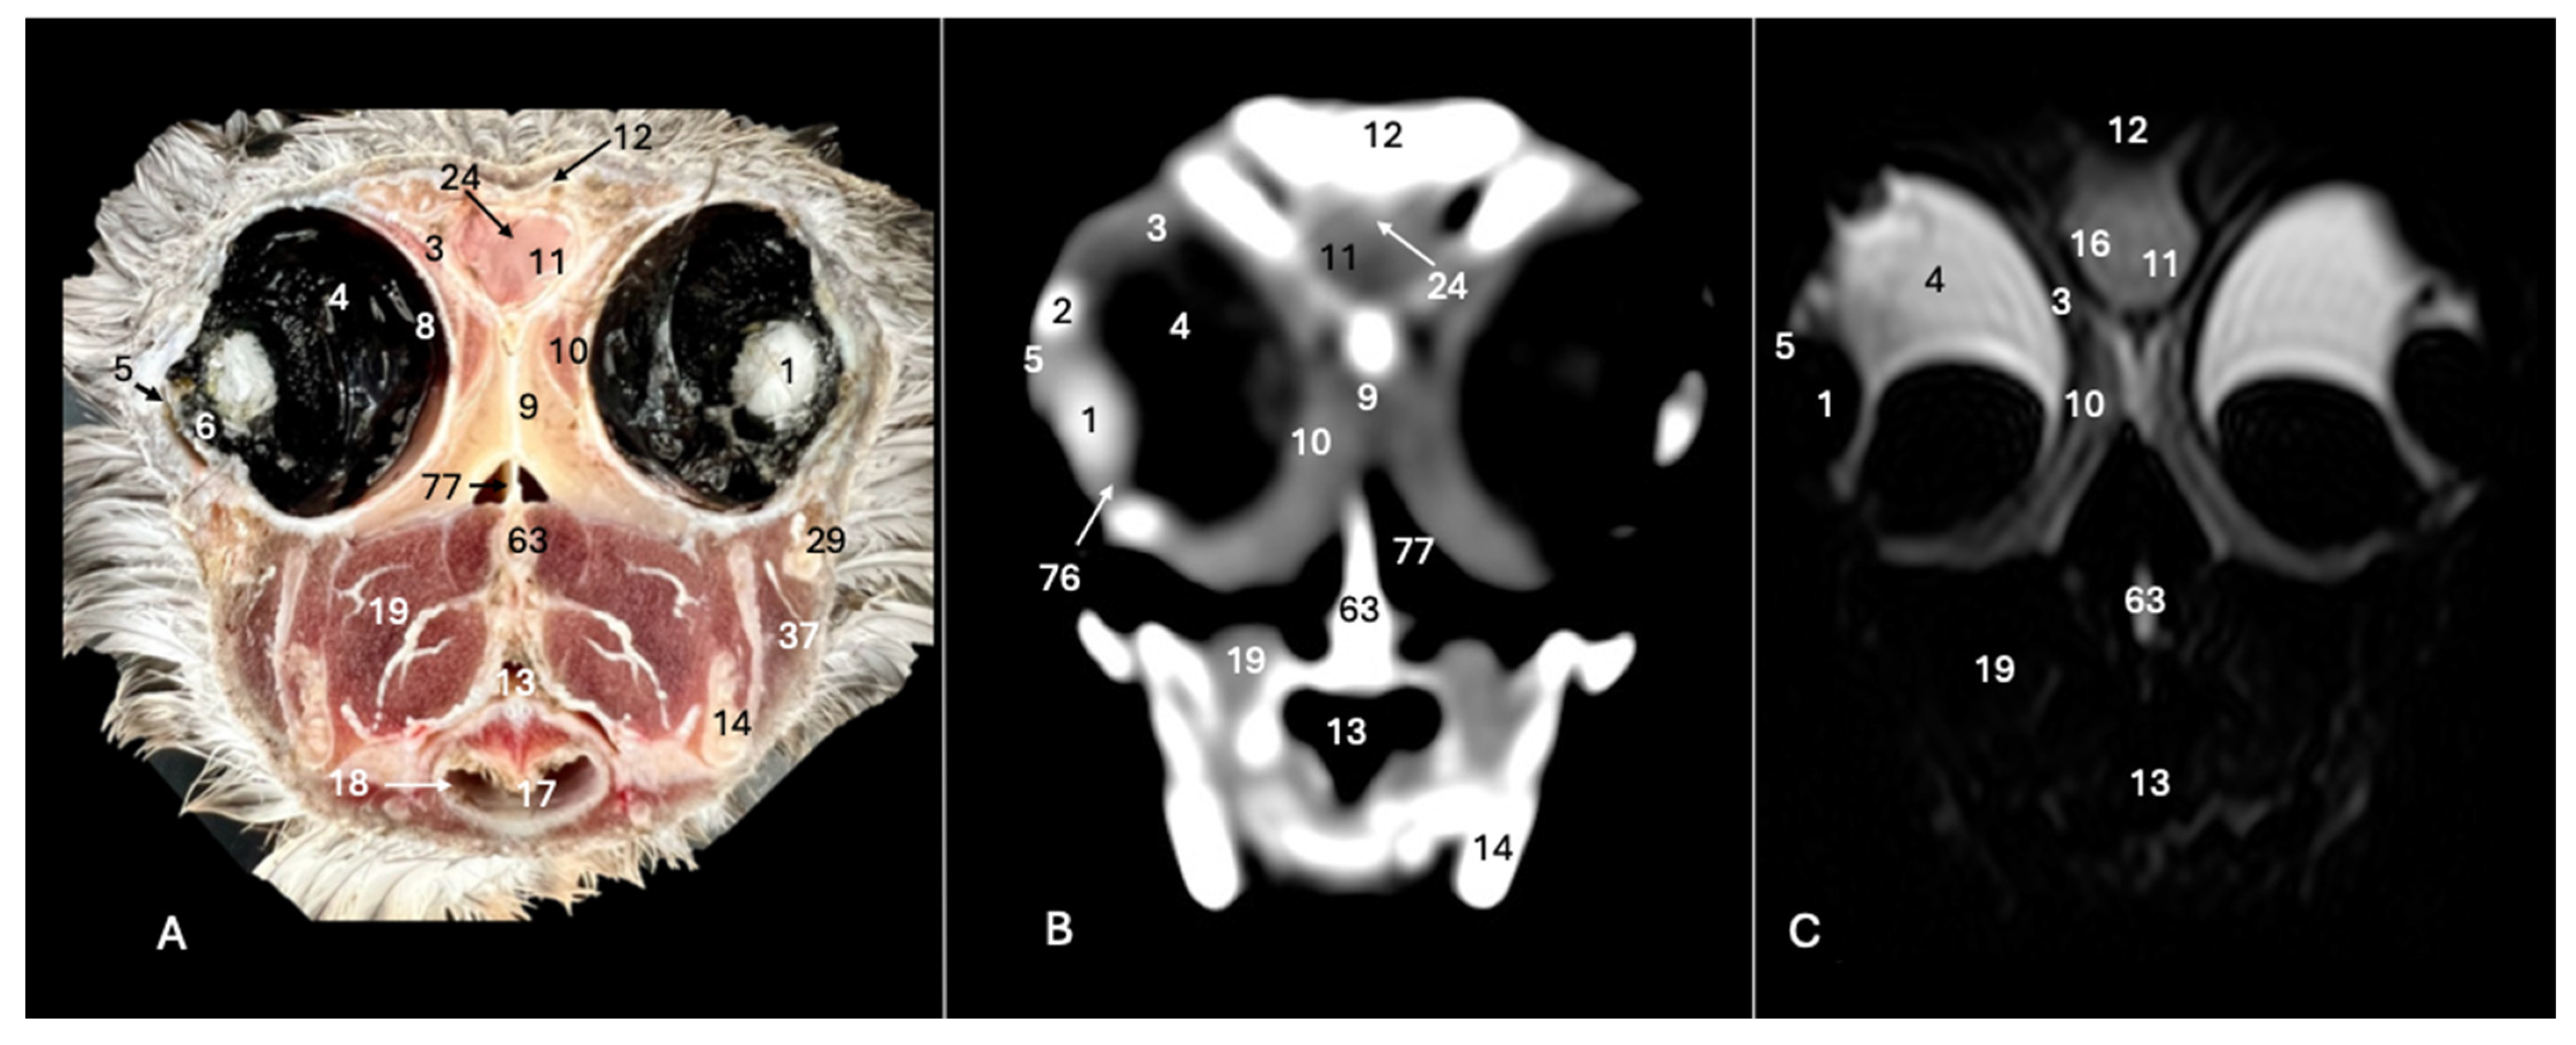

Figure 2. Anatomical cross-section (A), soft tissue CT window (B) and T2-weighted MR (C) transverse images of the Cory’s shearwater head at the level of the eyes, corresponding to line I in Figure 1. 1: Lent cristali; 2: sclerotic ossification; 3: sclera; 4: camera vitrea bulbi; 5: cornea; 6: camera anterior bulbi; 9: septum interorbitalis; 10: extraocular muscles; 11: olfactory bulb; 12: os frontale; 13: pharynx; 14: mandible; 16: cerebral hemisphere; 17: trachea; 18: tracheal ring; 19: musculus pterygoideus pars ventralis; 24: fissura longitudinalis cerebri; 29: processus postorbitalis; 37: musculus adductor mandibulae externus; 63: parasphenoid rostrum; 76: ciliary body; 77: choana.